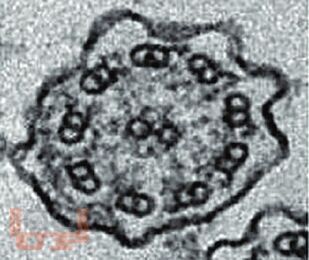

Монография посвящена одной из самых актуальных и насущных проблем педиатрии - кашлю. Детально разобраны механизмы кашля, дифференциальный диагноз заболеваний, сопровождающихся кашлем, методы дифференцированной терапии. Рассмотрены как собственно противокашлевые средства, так и мукоактивные, отхаркивающие препараты, облегчающие кашель. Представлены особенностимукоцилиарного клиренса и образования трахеобронхиального секрета в норме и при различной патологии легких у детей. Подробно освещены все классы современных препаратов, механизмы их действия и алгоритмы выбора. Приведены справочные таблицы. Освещены также немедикаментозные терапевтические подходы.